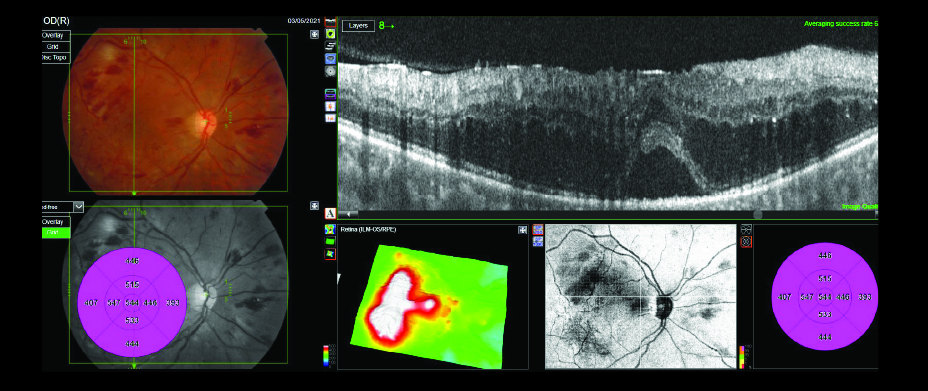

Case Study – Advanced PDR with Non-Perfusion and Macular Edema

33-year-old Caucasian female with history of myopia, vulvar cancer, family history of diabetes and liver cancer presented with a visual acuity of 20/200 (OD), 20/50 (OS). Intraocular pressures were measured 17mmHg (OD), 19mmHg (OS). A posterior subcapsular cataract was observed with all other ocular physiological characteristics normal.

3D Wide OCT Combination Scans, fluorescein angiography and fundus photos were obtained OU. Macular edema, subretinal fluid, intraretinal hemorrhages, cotton wool spots (CWS), nonperfusionable vessels and hemorrhages in the peripheral vessels were visualized OU.

Diagnosis: Advanced Proliferative Diabetic Retinopathy (PDR), retinal non-perfusion and macular edema OU

Treatment: Bevacizumab, PRP laser (OU)

Discussion: 45-degree fluorescein images, true-color photos of the retina and penetrating swept-source OCT scans helped to confirm and document the clinical findings